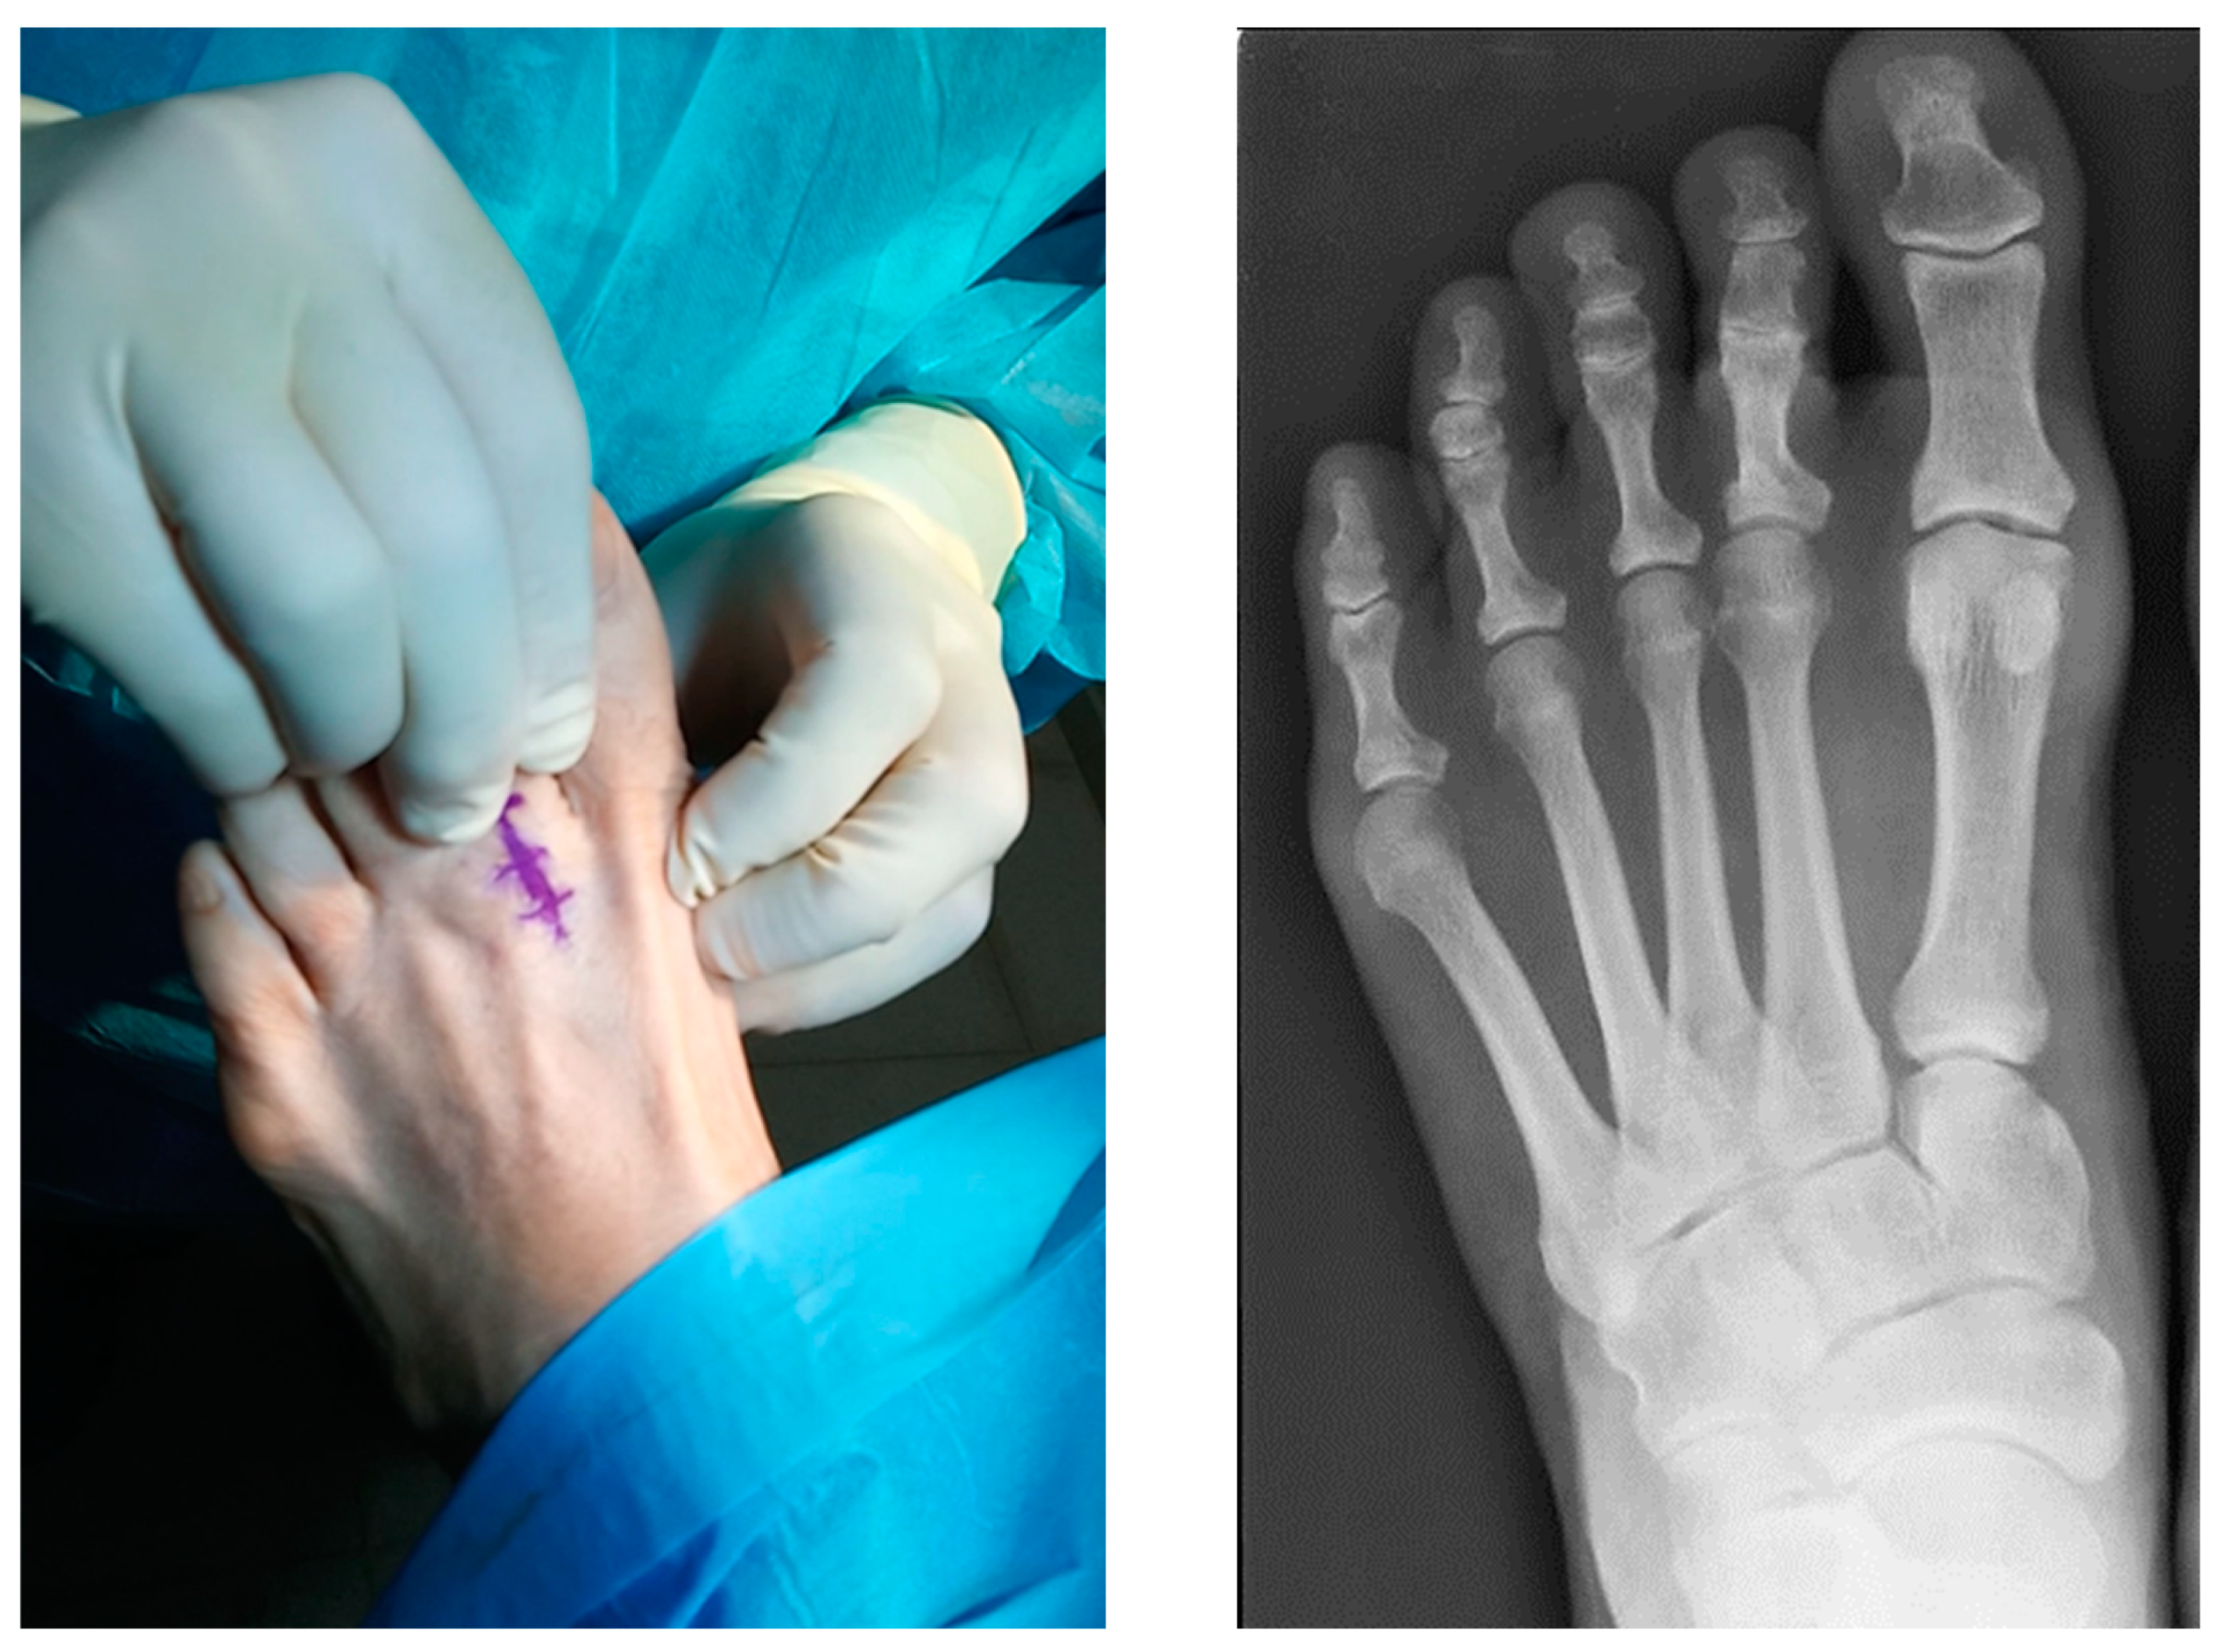

2.1. Case 1

2.2. Case 2